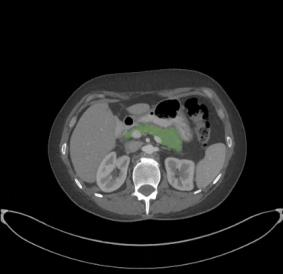

In this paper, we adopt 3D Convolutional Neural Networks to segment volumetric medical images. Although deep neural networks have been proven to be very effective on many 2D vision tasks, it is still challenging to apply them to 3D tasks due to the limited amount of annotated 3D data and limited computational resources. We propose a novel 3D-based coarse-to-fine framework to effectively and efficiently tackle these challenges. The proposed 3D-based framework outperforms the 2D counterpart to a large margin since it can leverage the rich spatial infor- mation along all three axes. We conduct experiments on two datasets which include healthy and pathological pancreases respectively, and achieve the current state-of-the-art in terms of Dice-S{\o}rensen Coefficient (DSC). On the NIH pancreas segmentation dataset, we outperform the previous best by an average of over 2%, and the worst case is improved by 7% to reach almost 70%, which indicates the reliability of our framework in clinical applications.